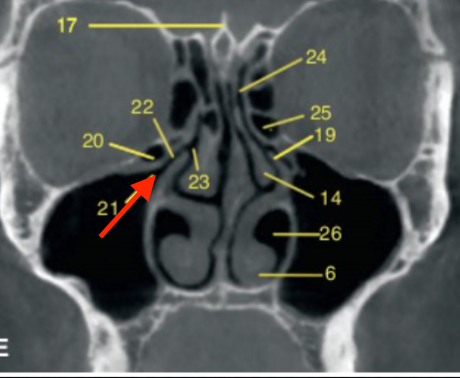

ostium (of maxillary sinus)

identify the structure

uncinate process

identify structure

sphenoid sinus

frontal sinus

ethmoid air cells

identify the structures

orbit

coronal

what plane